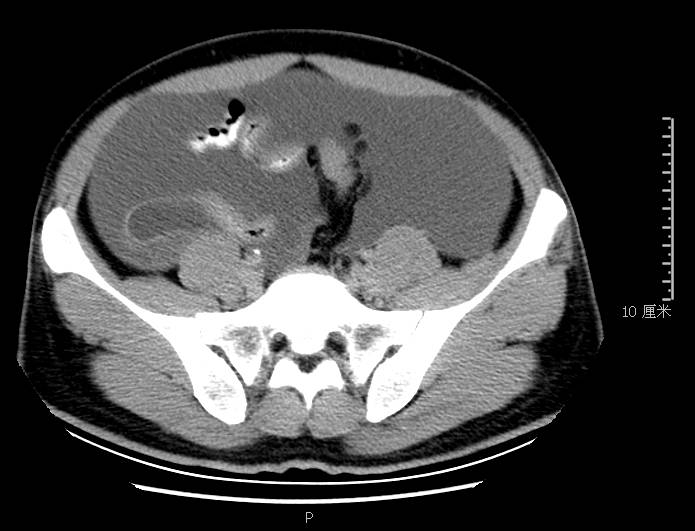

全腹CT:(1)结合病史考虑腹膜炎(见图2A),大量腹水;(2)右骼窝区管状样结构,考虑阑尾扩张(见图2B);(3)肝脏多发小囊肿(见图2C);(4)肝内胆管轻度扩张,建议隔期复查。

图2b扩张成管状阑尾

PET-CT检查:(1)腹盆腔大量积液,腹膜略厚,其间散在小淋巴结,代谢轻度增高,倾向腹膜炎可能性大,建议治疗后复查并密切复查肿瘤标志物;(2)双侧颈部领下、双侧腋窝淋巴略增大,代谢轻度增高,考虑炎性病变;(3)右肺下叶胸膜下钙化灶;(4)肝内多发囊肿,胆囊壁略毛糙;(5)右侧骼窝区细条形软组织影,代谢稍增高,考虑阑尾扩张。电子胃镜:(1)胃息肉(1枚己摘除);(2)反流性食管炎(*级A**);(3)慢性胃炎。电子肠镜未见结核、肿瘤性病变,未见阑尾开口扩张及周围组织红肿糜烂性病变,见图3。

本例确诊后对B超及CT再次回顾发现:腹腔、盆腔可见不均质中强回声包块,部分呈囊实状,腹膜增厚,大网膜成饼状(如图2A)和肝周可见不均质中强回声弧形压迹、脾周可见不均质中强回声包饶,肝脏成扇贝样改变(如图2C),但在诊断报告中未提及。有学者发现mantle和scalloping(如图2A,2C)在PMP中具有代表性,且mantle较scalloping更为常见,若mantel征同时伴有大小不一的囊性改变,则更具诊断价值。

图2c肝脏成扇贝样改变(肝脏因为受肿瘤实质性或囊性组织压迫而其实质却未受侵犯,于是在一处或多处呈下凹状或扇形皱褶状(scalloping)

与此同时,还应与肝硬化腹水、妇科肿瘤、肠梗阻等疾病相鉴别。此患者为男性,全腹CT及PET-CT均提示阑尾扩张,很大可能来源于阑尾黏液性肿瘤。阑尾黏性肿瘤早期可无任何症状,随着瘤体堵塞阑尾,累及浆膜下层,播散至腹盆腔,可形成大量的黏液性腹水,又称“胶腹”,则可出现腹痛、腹胀、腹围增加等症状。